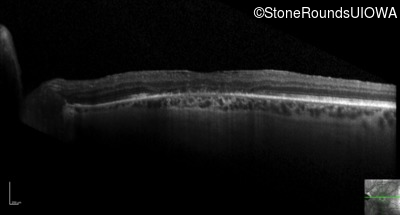

Optical Coherence Tomography - Right - 20/32 +1

Exemplar / OCT Stack

OCT Stack